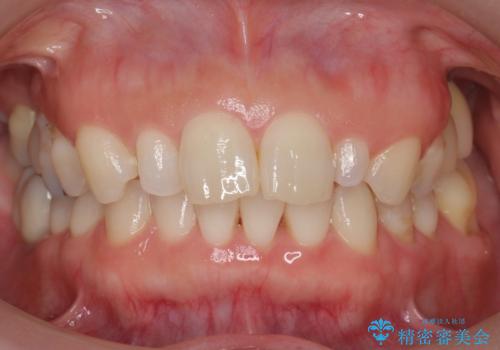

前歯が大きいのが気になる セラミックで整えたい

- 前歯が大きいのを揃えたいとのことでした。

少し削って長さを短くして様子を見ましたが、どうしても気になるとのことでした。

隣の前歯が小さいため、4本被せてバランスをとりました。

4本セラミックにすると大きさだけでなく、色も揃えられるのでおすすめです。